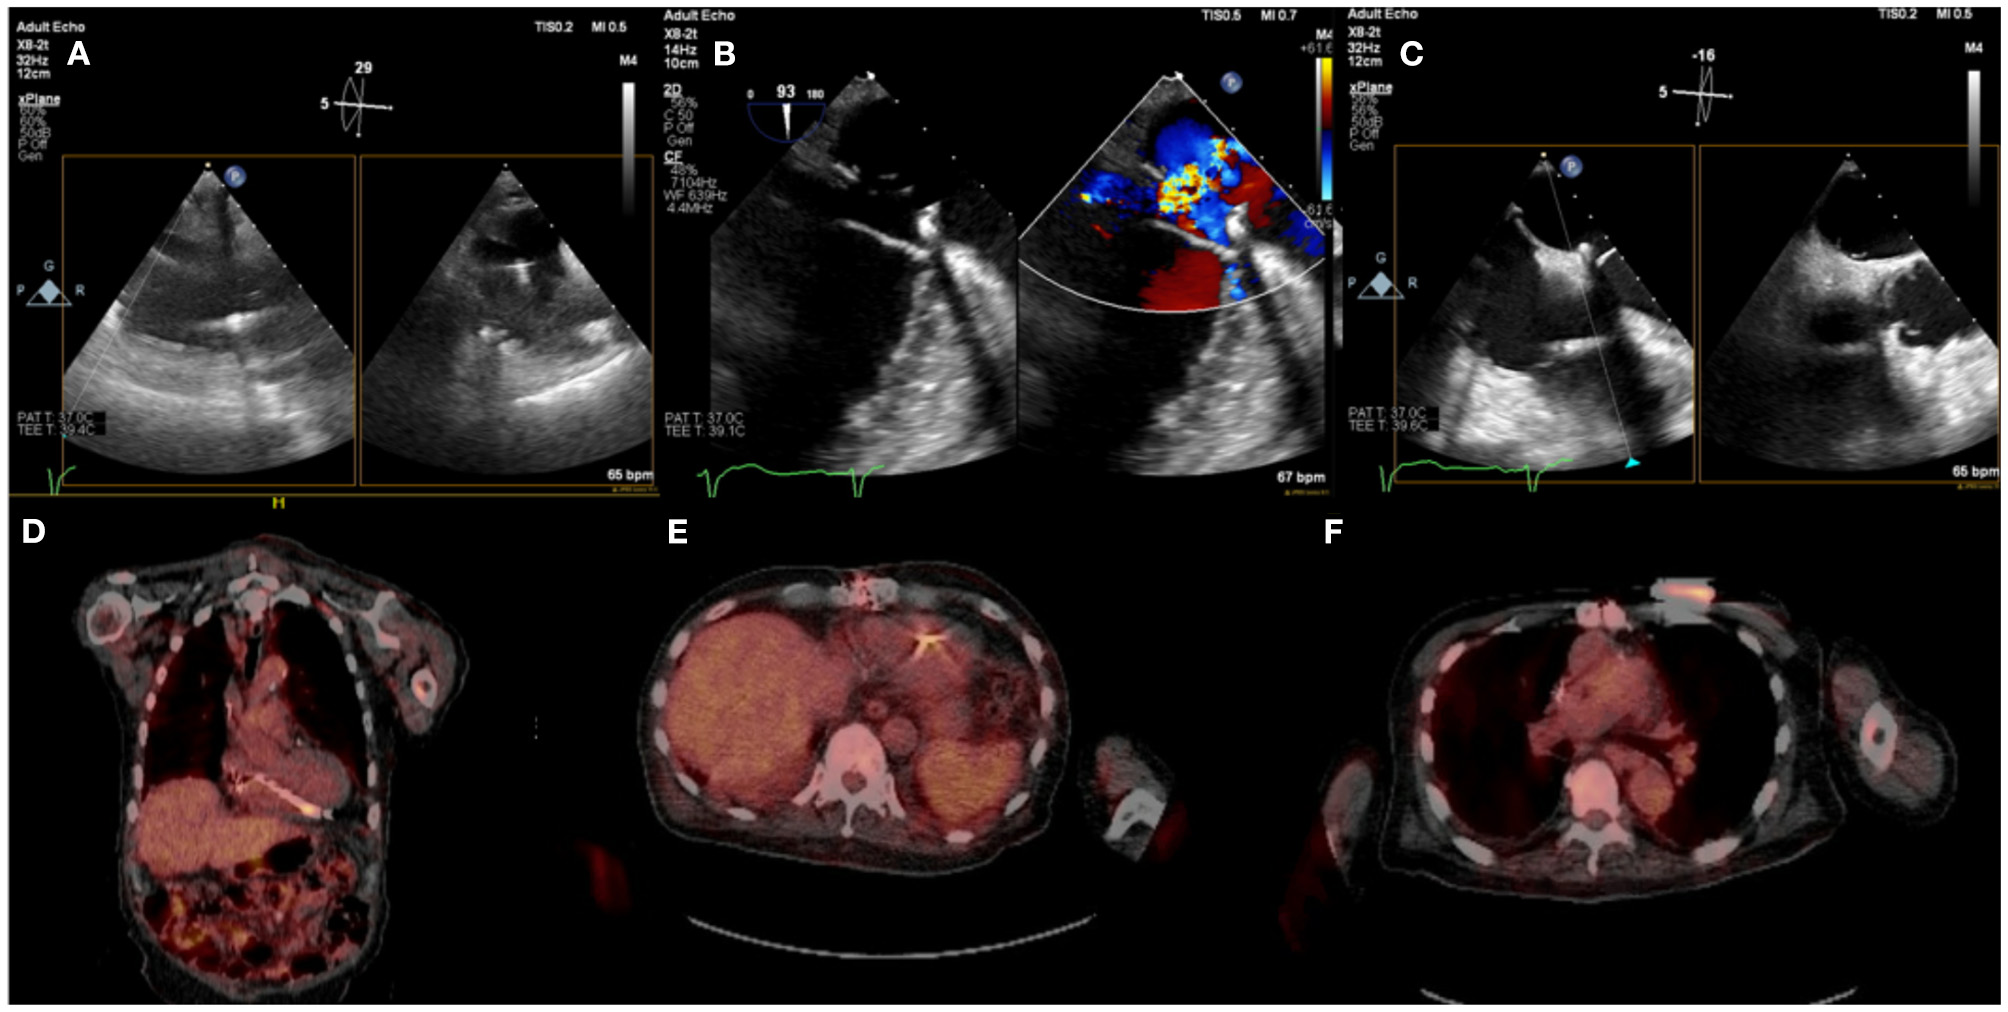

In a small percentage of patients with suspected infection and non-diagnostic TEE or when TEE cannot be performed, alternative imaging methods are indicated (5, 11). A functional approach based on nuclear imaging using 18F-FDG PET-CT or radiolabeled WBC scintigraphy, has been incorporated to the 2015 ESC guidelines for management of endocarditis and the most recent 2020 European Heart Rhythm Association consensus for management of CIED infections (1, 18). The performance of 18F-FDG PET-CT in CIED infections was studied in a meta analysis by Juneau et al. and showed its high diagnostic accuracy with 87% sensitivity and 95% specificity for the diagnosis of IE (6). In addition, 18F-FDG PET-CT has the advantage of allowing imaging of multiple sites of possible infection (pocket/generator, leads) in one examination with a high diagnostic yield for septic emboli to the lungs or very rarely the bone structures which has management implications (i.e. need for longer antibiotic course with good bone penetrance in spondylodiscititis) (19, 20) (Figure 4).

Figure 4

Eighty five year-old male with history ischemic cardiomyopathy s/p dual-chamber ICD for primary prevention, history of CABG and mitral valve repair presented with persistent MRSA bacteremia. TEE showed small linear echodensities attached to right atrial lead (A), multiple small echodensities attached to mitral ring and moderate mitral regurgitation (B). The RV showed no vegetations with normal tricuspid valve (C). 18F-FDG PET-CT was obtained to assess extent of infection and showed focal uptake along the RV lead (D,E). Left chest wall ICD showed focal uptake but no pocket uptake to suggest pocket infection (F). The patient was deemed to have a prohibitive risk for redo cardiac surgery and was treated medically. He passed away 2 months after the diagnosis of CIED systemic infection with MRSA endocarditis.

Caution must be used when interpreting 18F-FDG PET-CT in early CIEDs (<2 months) as physiologic FDG uptake can be present without the presence of infection. Other disadvantages of using 18F-FDG PET-CT are high cost, not widely available, radiation, patient preparation and need for trained personal.